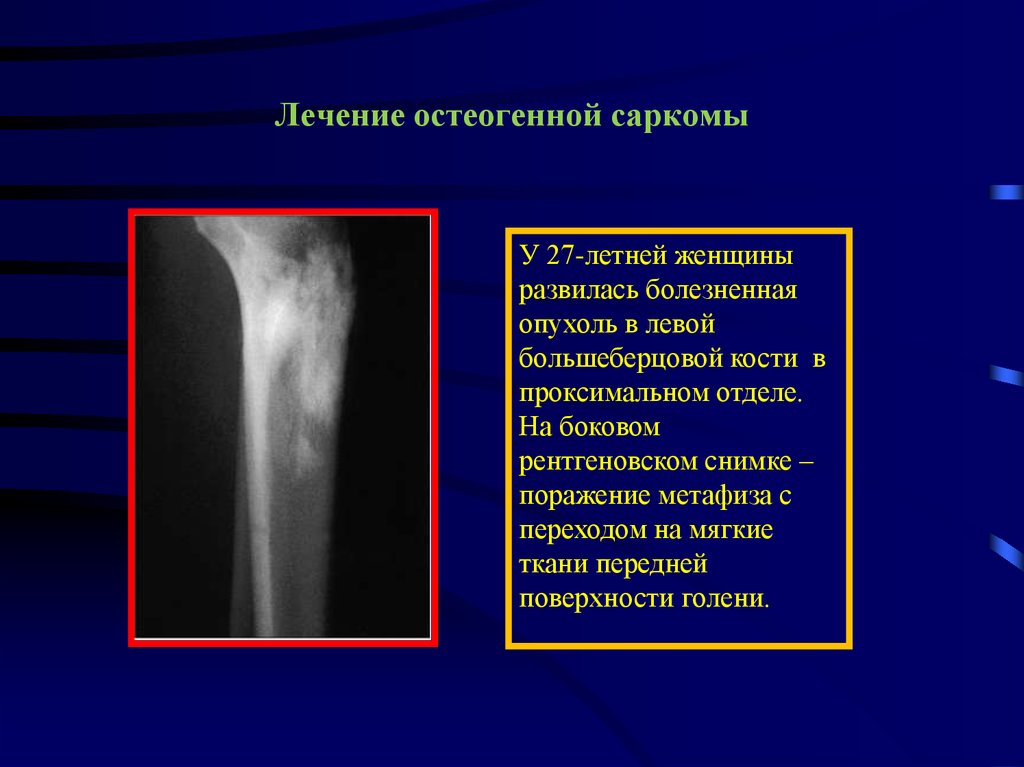

Рентгенологическая картина остеогенной саркомы кости - 98 фото